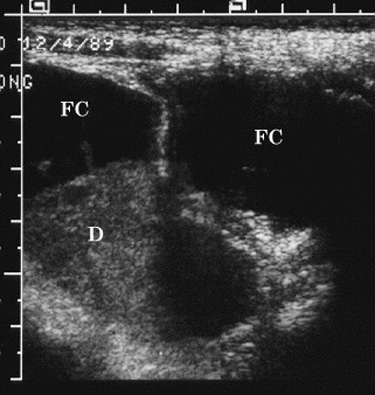

Diagnosing Appendicitis With Imaging

Pelvic inflammatory disease Ultrasound of Appendicitis. Appendix diameter. is larger than 6 mm. PACS BIDMC. Note how round appendix is despite compression with ultrasound Diagnosing Appendicitis with Imaging Author: hgunn Created Date: ... Fetch Doc